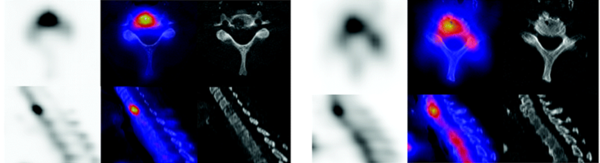

Une autre indication recommandée de la technique est la localisation précise d’une douleur rachidienne potentiellement pluri-factorielle (1, 2). La fixation du traceur scintigraphique sur le front ostéoblastique de remodelage osseux permet de localiser l’étiologie des douleurs.

La réalisation d’un SPECT/CT préalablement à une infiltration facettaire permet de préciser et localiser le site le plus actif pouvant être la cible de l’infiltration dont la probabilité d’efficacité est alors améliorée.(3) (fig. 4)

Figure 4 - Arthrose postérieure L4-L5 active